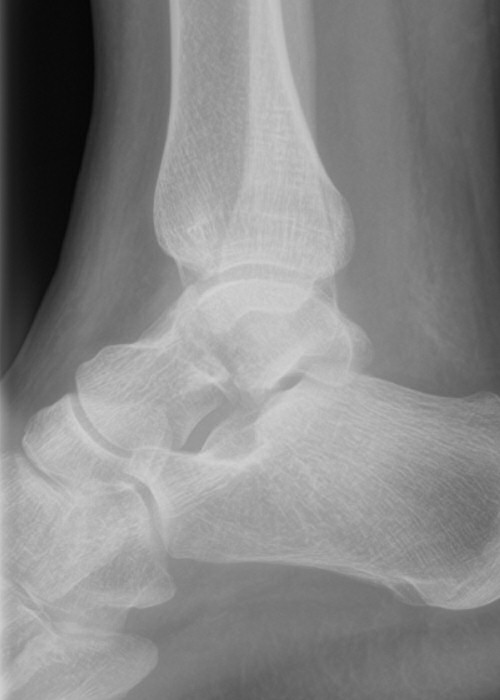

Slätröntgen vid misstanke om skelettskada i foten, DT krävs för att kartlägga fraktur i talus [1].

Osteokondrala skador

- Relativt vanligt vid distorsionsvåld [1], eller upprepat mikrotrauma [4]

- Kan ge knäppningar, låsningar, skarp smärta vid belastning, svullnad [1, 4]

- Ses ibland på slätröntgen, annars krävs MR eller artroskopi för diagnos [1]